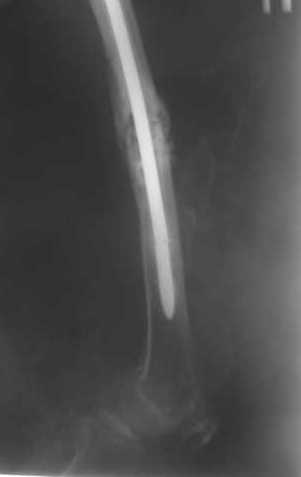

Как обещал, выкладываю рентгенограммы нашего пациента.

Пациенту М., 30-ти лет, 1,5 года назад в одной из московских больниц был выполнен остеосинтез бедренной кости штифтом UFN (диаметр штифта 9 мм).

К нам больной поступил с признаками ложного сустава бедренной кости, перелома

штифта и дистального блокирующего винта (images 1,2,3).

27 марта выполнено удаление блокирующих винтов (сломанный винт пришлось высверливать цапфен-бором), сломанного штифта (дистальный фрагмент удален через канал, образованный разверткой из коленного сустава - image 4),

рассверливание костно-мозгового канала, реостеосинтез штифтом UFN (при проведении штифта в дистальном отломке мы использовали поляризующий винт, диаметр штифта 10 мм). После операции в связи гемартрозом дважды (на 1 и 3 сутки) выполняли пункцию коленного сустава. Сейчас признаков скопления жидкости в полости сустава нет. Послеоперационные рентгенограммы - images 5, 6, 7.